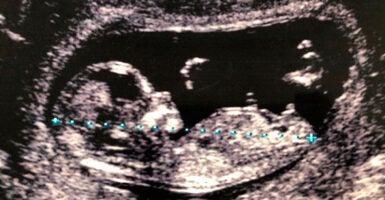

Giving Preborn Twins With a Rare Disorder the Lifesaving Chance They Deserve